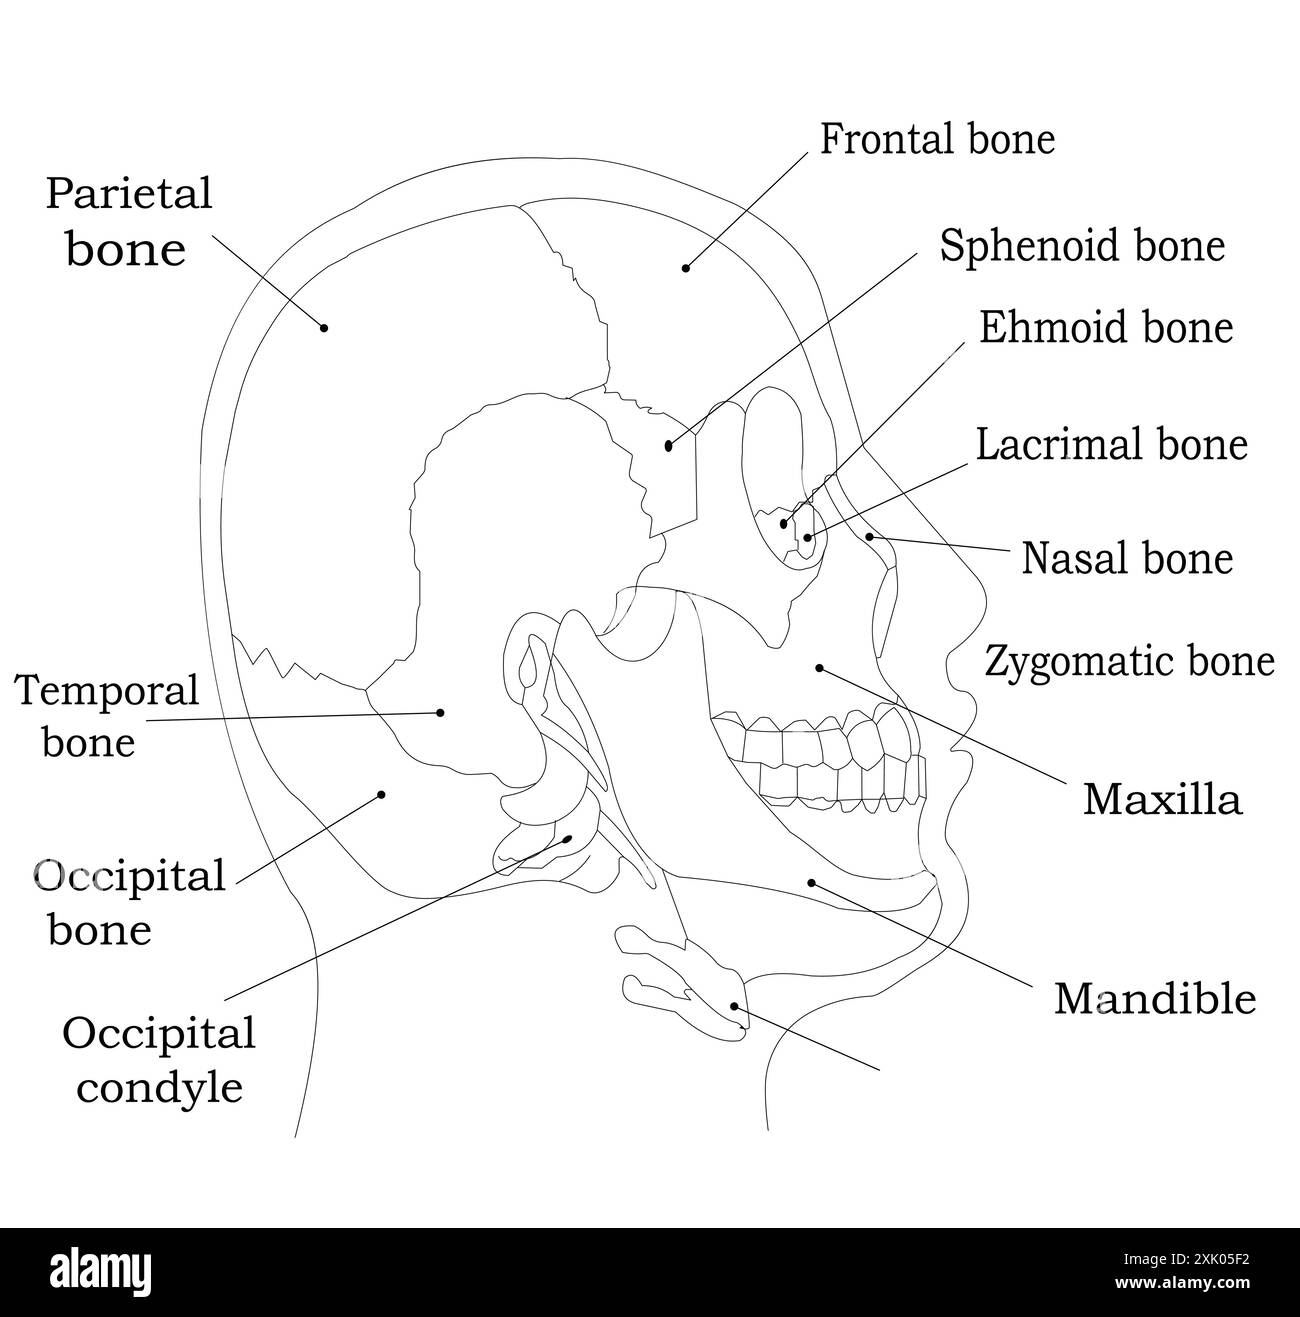

Schéma étiqueté des os du crâne humain - illustration de la vue anatomique latérale Illustration de Vecteurhttps://www.alamyimages.fr/image-license-details/?v=1https://www.alamyimages.fr/schema-etiquete-des-os-du-crane-humain-illustration-de-la-vue-anatomique-laterale-image614045686.html

Schéma étiqueté des os du crâne humain - illustration de la vue anatomique latérale Illustration de Vecteurhttps://www.alamyimages.fr/image-license-details/?v=1https://www.alamyimages.fr/schema-etiquete-des-os-du-crane-humain-illustration-de-la-vue-anatomique-laterale-image614045686.htmlRF2XK05F2–Schéma étiqueté des os du crâne humain - illustration de la vue anatomique latérale